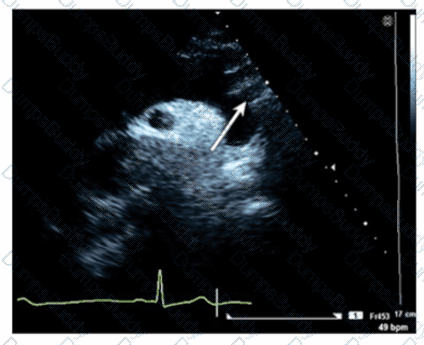

Which patient positioning is best for obtaining the waveform seen in this image obtained by a non-imaging transducer?